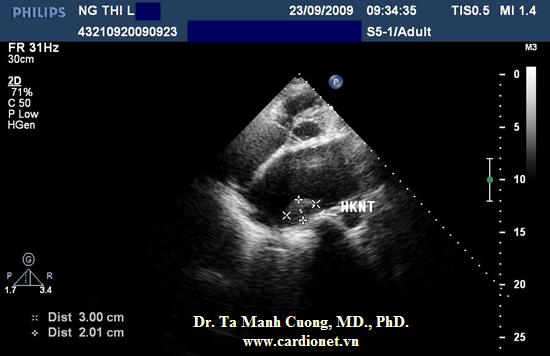

Hình ảnh huyết khối khá lớn (kích thước 2 x 3 cm) của người mang van hai lá cơ học trên mặt cắt siêu âm trục ngắn